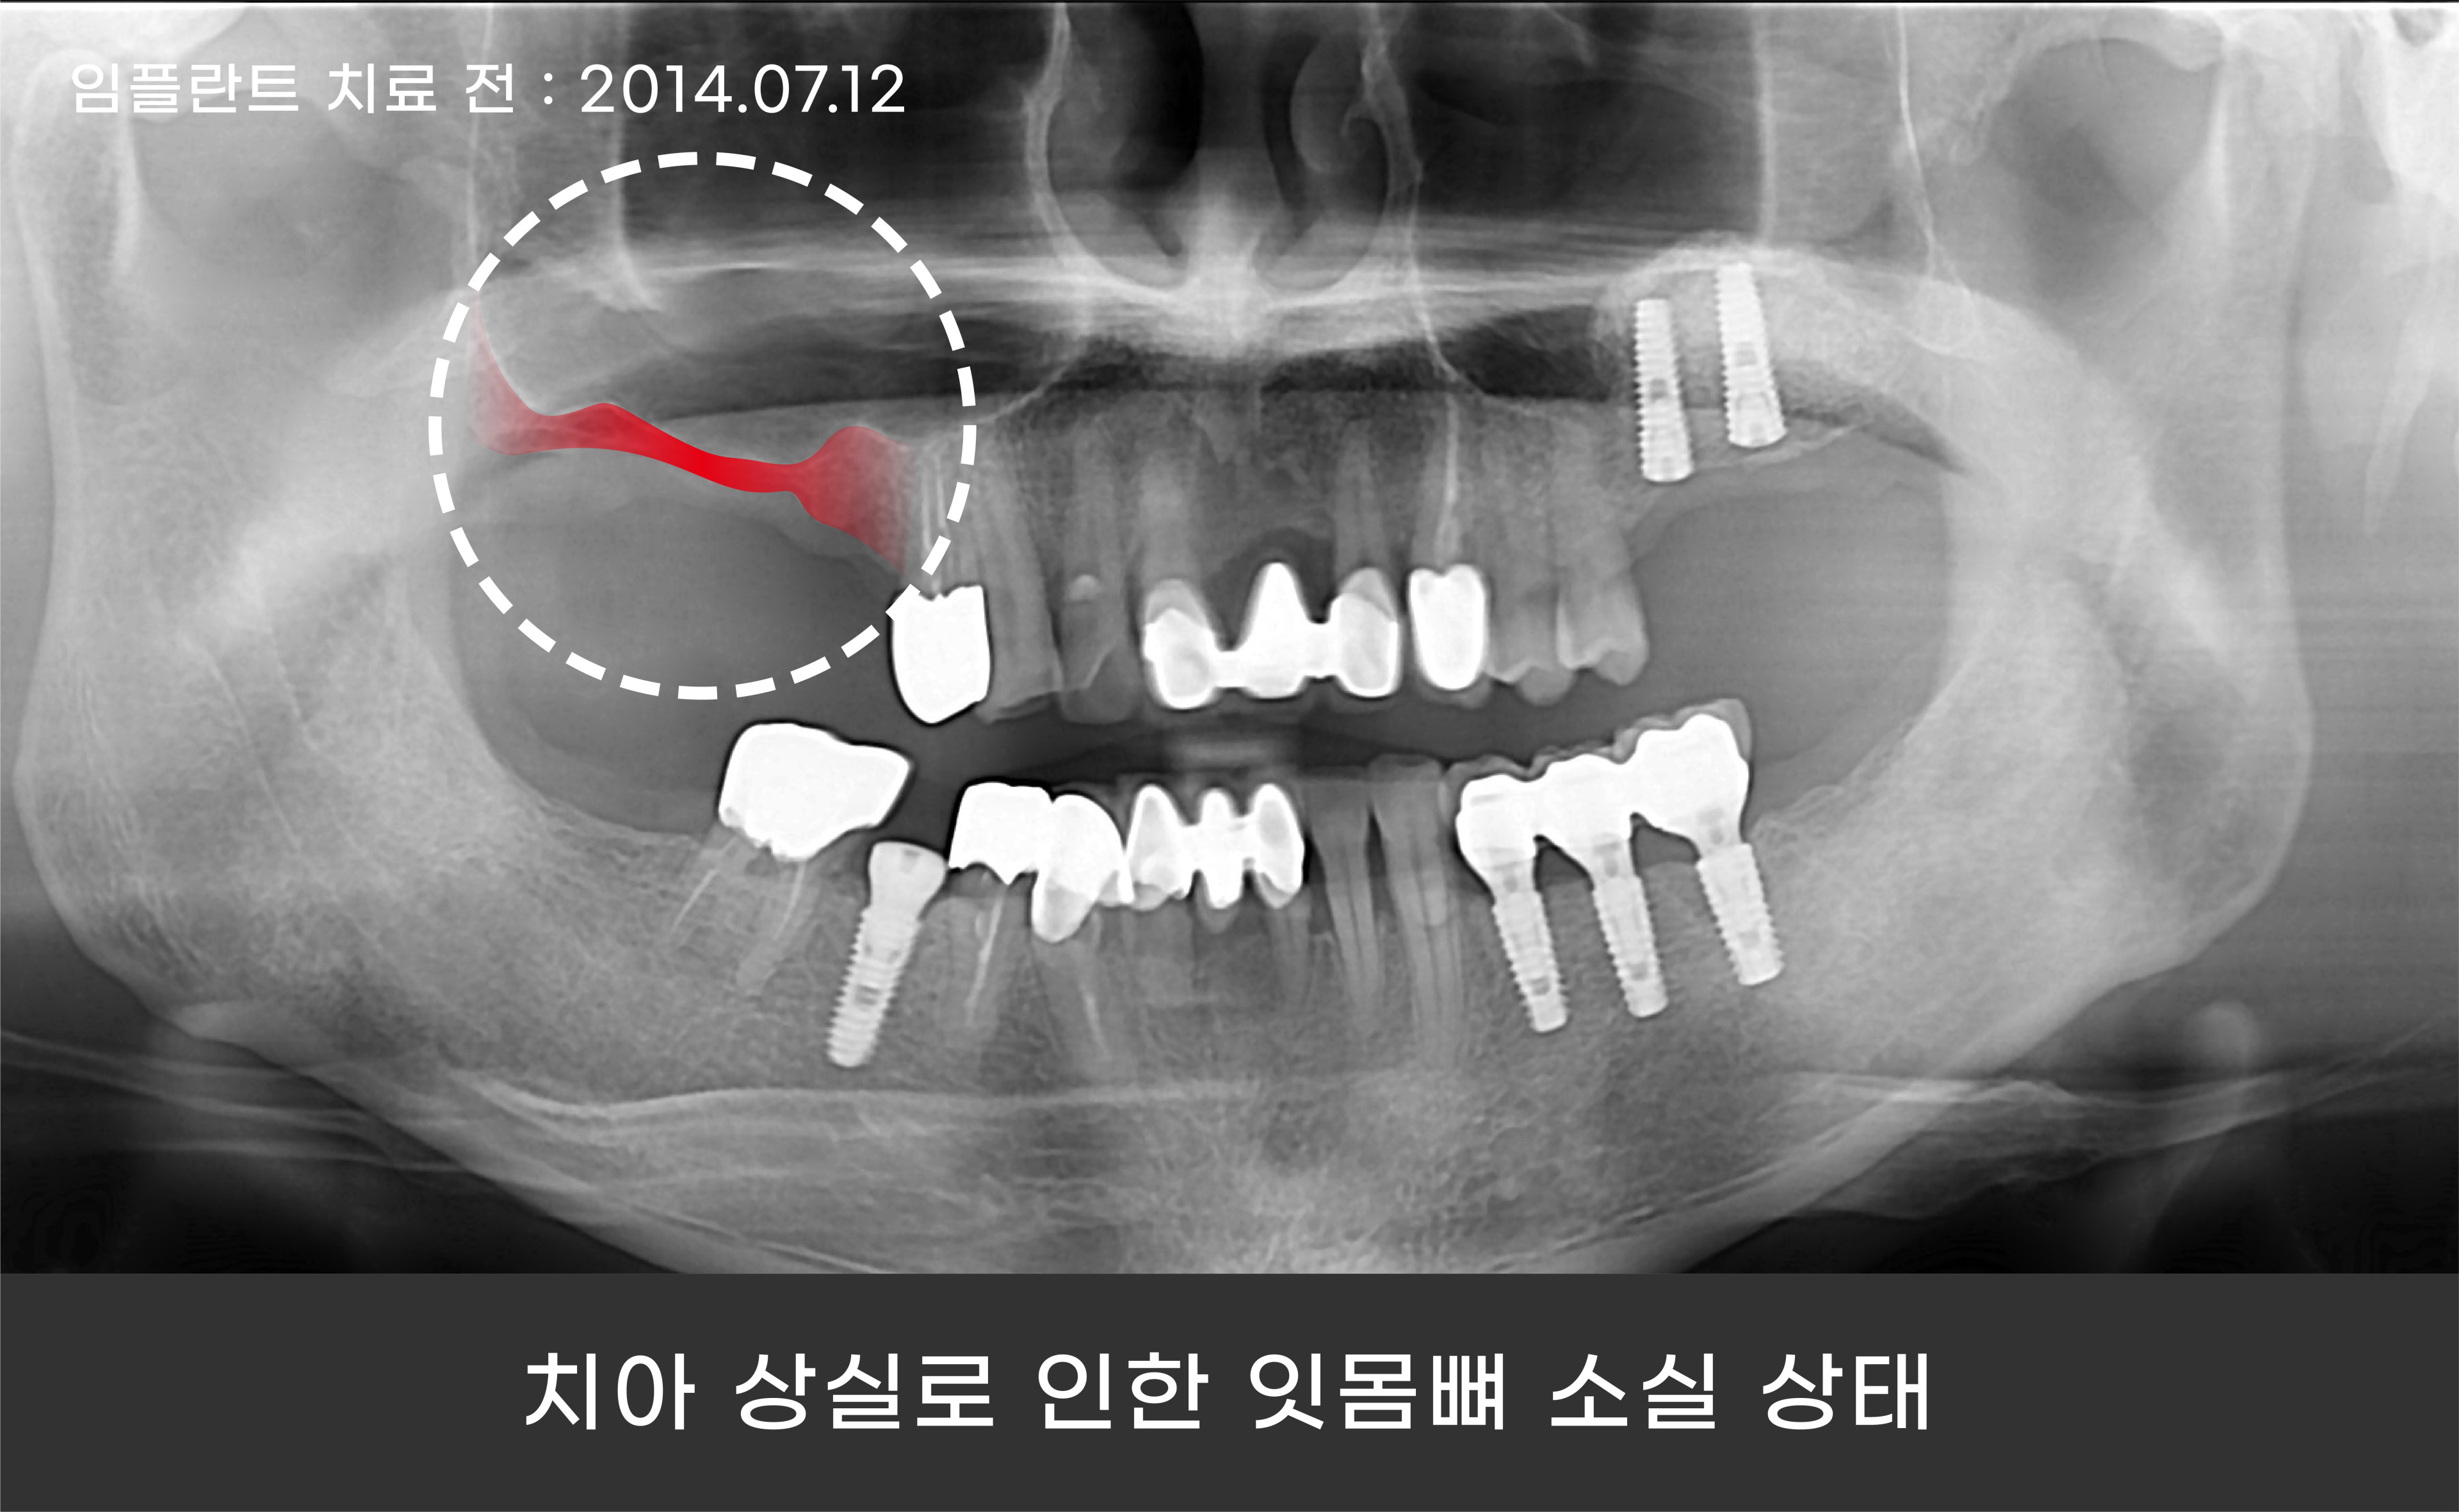

그리고 환자분께서는 상악 어금니 쪽을 상실한 채로

오랫동안 방치하셨는지 잇몸뼈 소실 또한 심각한 상태였는데요.

임플란트 재수술과 상악동거상술을 통해 임플란트 치료를 진행하기로 했습니다.